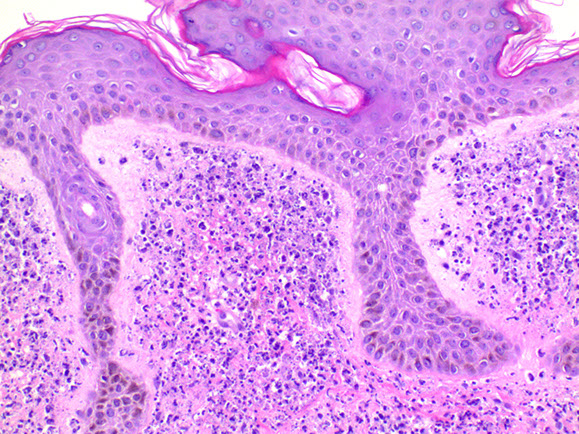

Micro: "dilapidated brick wall" appearance of acantholysis

- also see acanthosis

- pinkish halo surrounds nuclei

Hailey-Hailey disease